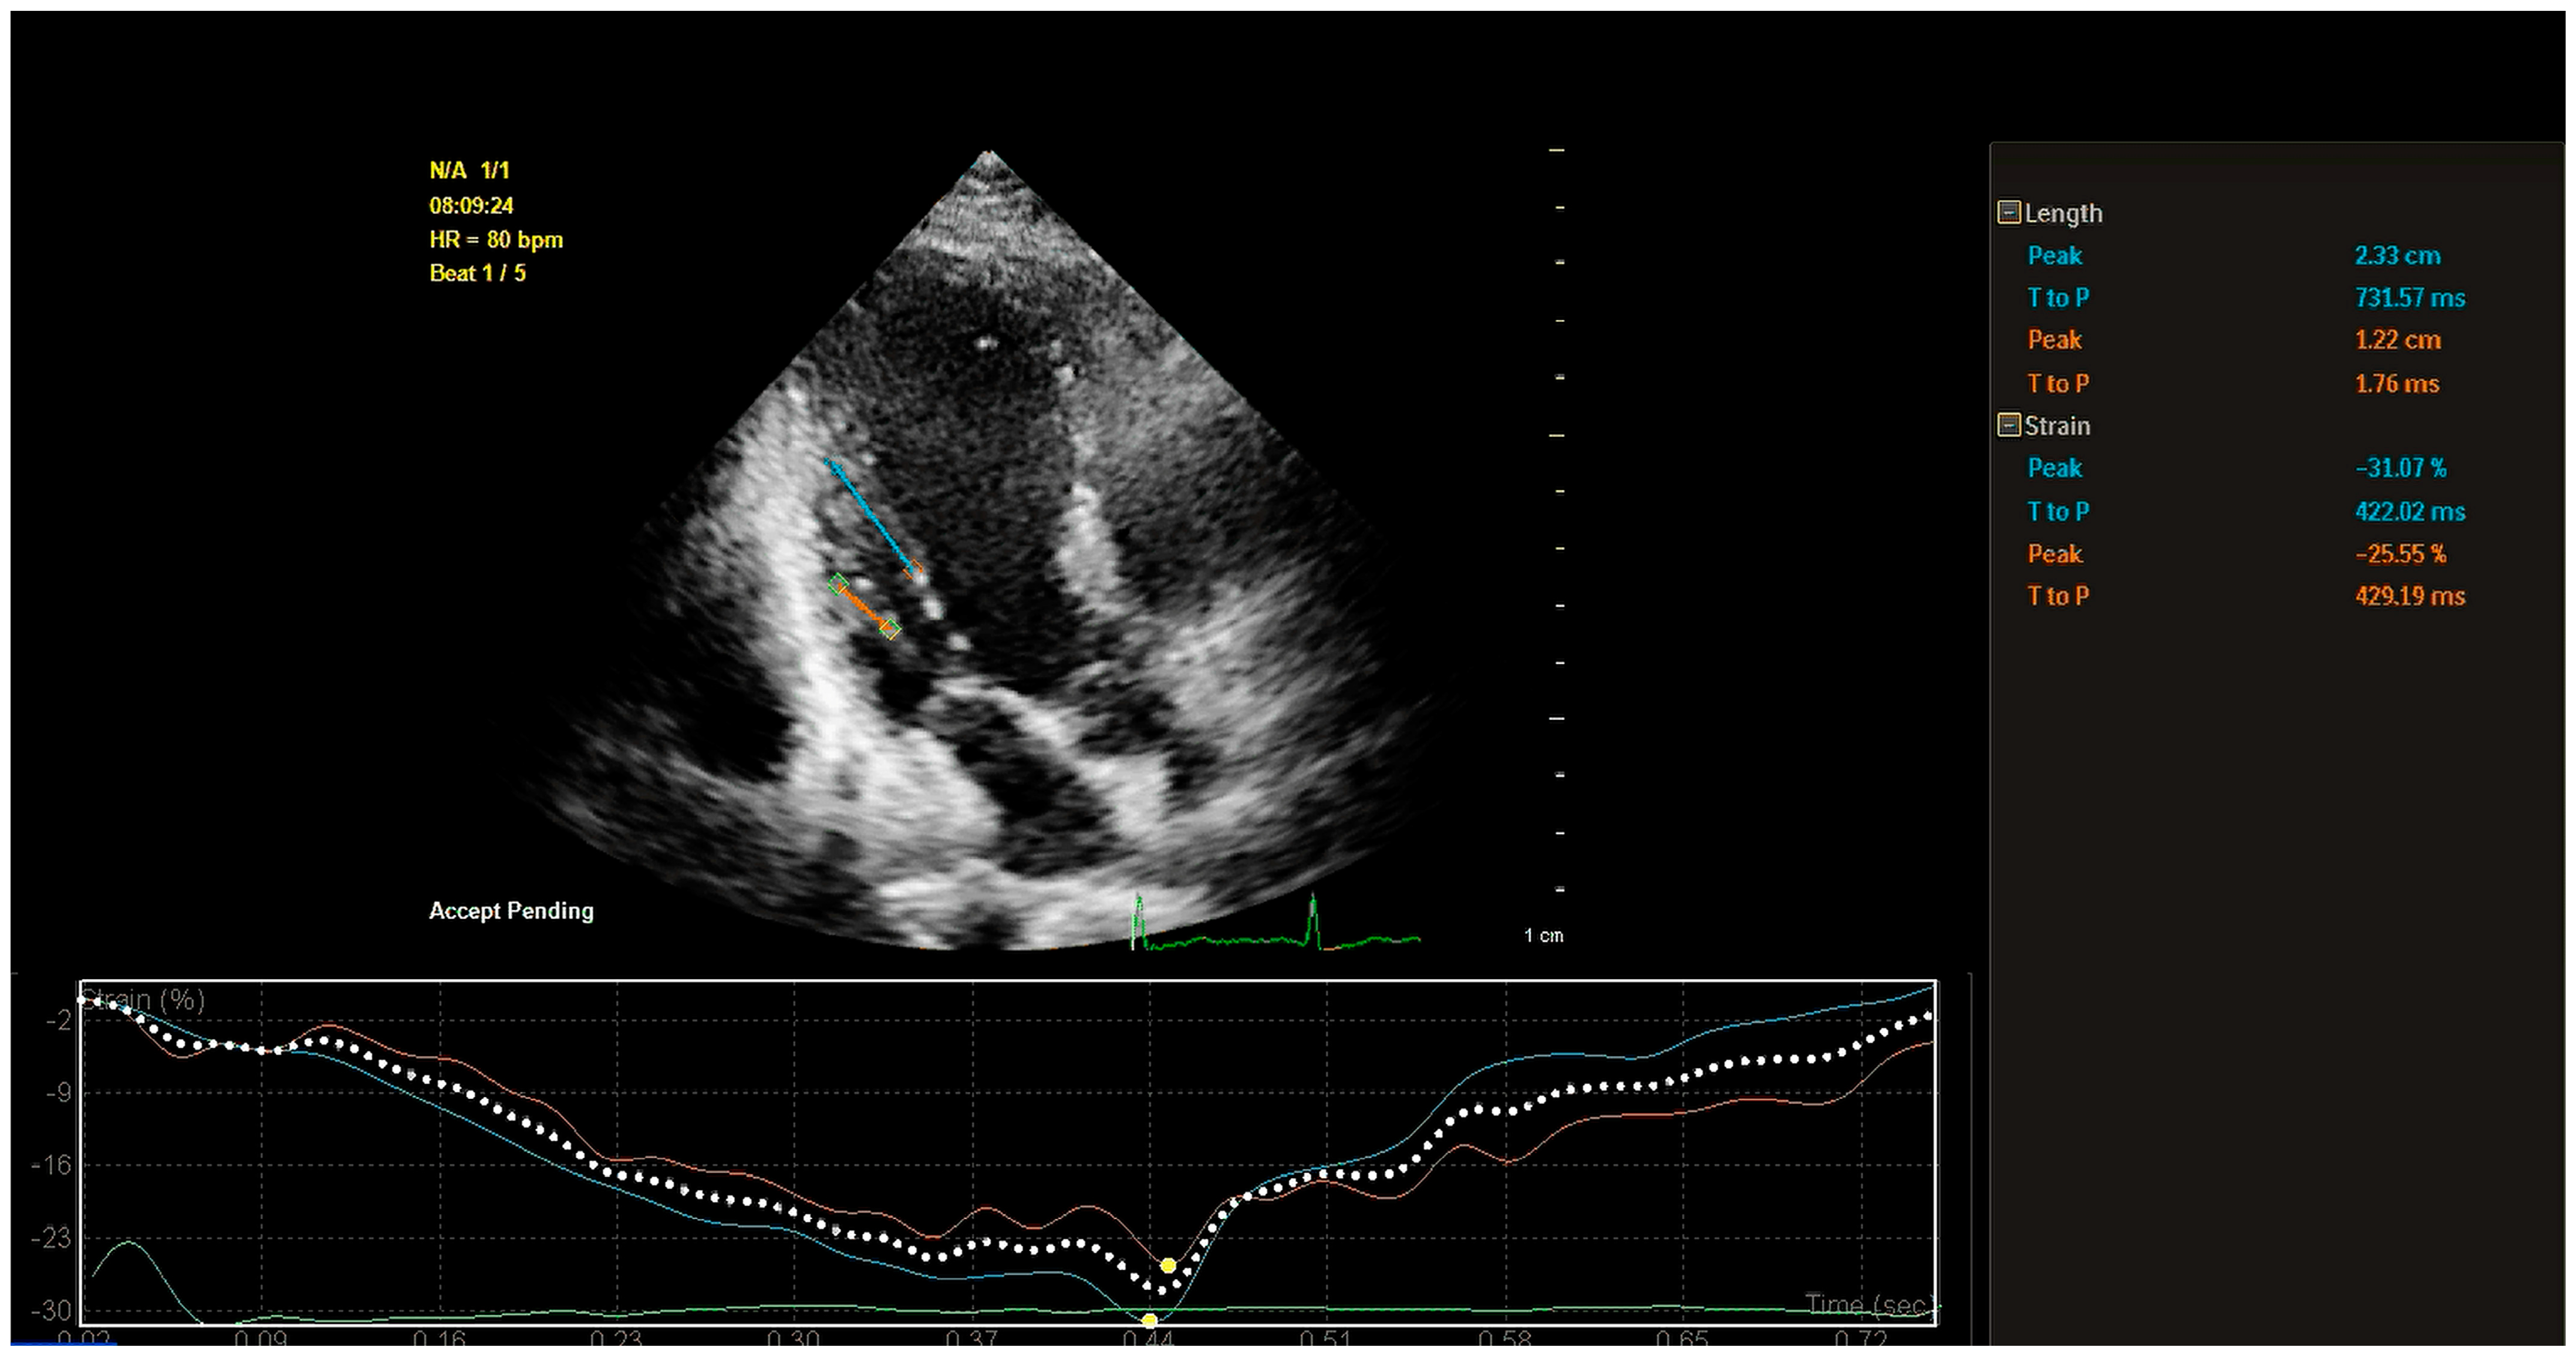

5.2. Assessment of PM Function

5.2.2. Quantitative Assessment of PM Function